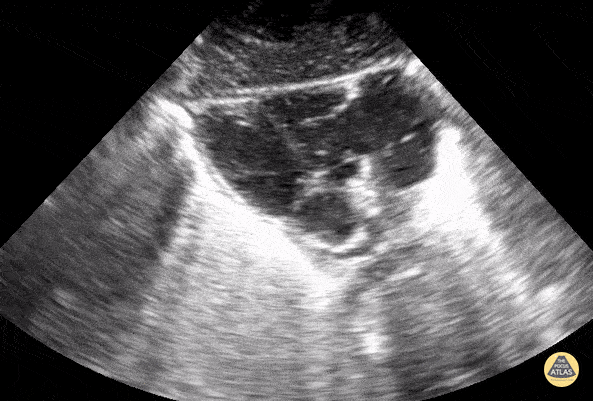

Cardiac arrest- standstill. Contributor: Elad Machtey, MD, BC Children's Hospital

https://www.thepocusatlas.com/pedscardiac